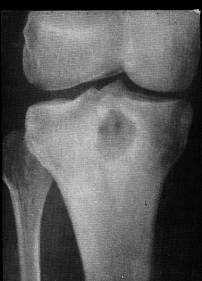

У міру затихання запалення під впливом антибактеріальної або хірургічного лікування швидко зменшується остеопороз і утворюється зрощення позбавлених хряща кісток, формується кістковий анкілоз (рис. 7).

Мал. 7. Кістковий анкілоз в колінному суглобі після перенесеного гонорейного артриту.